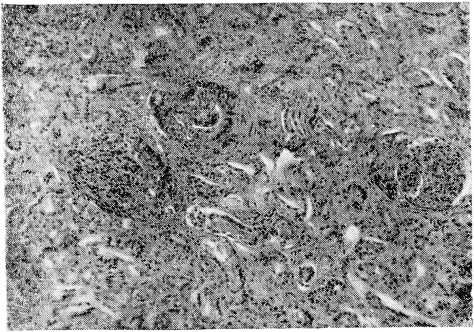

Рис. 1. Гломерулонефрит при болезни Шенлейн—Геноха. Видны увеличенные клубочки, богатые ядрами, образование полулуний. (Ок. 7, об. 8)

Микроскопическое исследование (окраска гематоксилин-эозином, пикрофуксином, на фибрин по Вейгерту): Почки — клубочки значительно увеличены, выполняют просветы капсул, значительно увеличено количество эндотелиальных элементов, обилие лейкоцитов. Плазматическое пропитывание, а местами фибриноидный некроз сосудистых петель клубочков и афферентных сосудов. Пролиферация эпителия капсул Шумлянского — Боумена, местами с образованием полулуний. В просветах капсул встречаются скопления эритроцитов и белковой массы. Зернистая дистрофия эпителия канальцев, в просветах которых скопления эритроцитов. В ин- терстиции—лимфоидные инфильтраты, расположенные преимущественно вокруг клубочков. Сердце- эпикард отечен, разрыхлен с круглоклеточными инфильтратами.. Мелкие артерии и вены эпикарда с пролиферацией адвентициальных и эндотелиальных элементов и сужением просвета. Аналогичные изменения в мелких сосудах миокарда. Стенка тонкой кишки: отек и кровоизляния в подслизистом слое и серозном покрове. Набухание и пролиферация эндотелия капилляров. Местами клеточные муфты вокруг мелких артерий. Кожа: множественные мелкие кровоизлияния, в дерме и подкожной клетчатке. Выраженная пролиферация эндотелия капилляров, мелких артерий и вен. Периваскулярные клеточные инфильтраты, преимущественно из полинуклеаров; последние местами густо инфильтрируют и самую стенку сосудов..

Микроскопическое исследование. Почка — большая часть клубочков увеличена в размерах за счет пролиферации эндотелия и накопления лейкоцитов в просветах сосудистых петель; увеличенные клубочки почти целиком выполняют просветы капсул. Некроз части сосудистых петель. Отдельные клубочки деформированы, имеют лопастную форму, бедны клеточными элементами и частично фиброти- зированы. Отмечается очаговое утолщение капсулы клубочков и образование полулуний. Дистрофия эпителия мочевых канальцев, в просвете их цилиндры и кровь. Набухание и фибриноидный некроз стенки мелких артерий и артериол почки, пролиферация эндотелия. Местами разрастание межуточной соединительной ткани. В интерсти- ции почки видны круглоклеточные и лейкоцитарные инфильтраты, расположенные преимущественно вокруг клубочков и мелких артерий. Местами лейкоциты инфильтрируют стенки мелких артерий, образуя вокруг последних значительные муфты. Сердце: Деструкция стенки мелких артерий и артериол миокарда с разволокнением и набуханием, а местами и фибриноидным некрозом, пролиферацией эндотелия и образованием небольших адвентициальных клеточных муфт. Селезенка: множественные мелкие очажки некроза в пульпе, редукция фолликулов, местами картины эндопериваскулита. Стенка пищевода: небольшие язвы слизистой оболочки. В подслизистом слое и в ад- вентиции пищевода мелкие артерии в состоянии фибриноидного некроза, а местами и полной деструкции с широкими эозинофильными муфтами вокруг них. Резкое умень- щение просвета и утолщение стенки некоторых сосудов, встречаются тромбы в различной стадии организации. Стенка кишки: обширные кровоизлияния в подслизистом и мышечном слоях, местами пропитывание кровью всей стенки, пролиферация эндотелия капилляров с почти полным стиранием их просвета. Пролиферация эндотелиальных клеток и адвентициальных элементов стенки мелких артерий и вен. Встречаются периваскулярные лейкоцитарные инфильтраты.